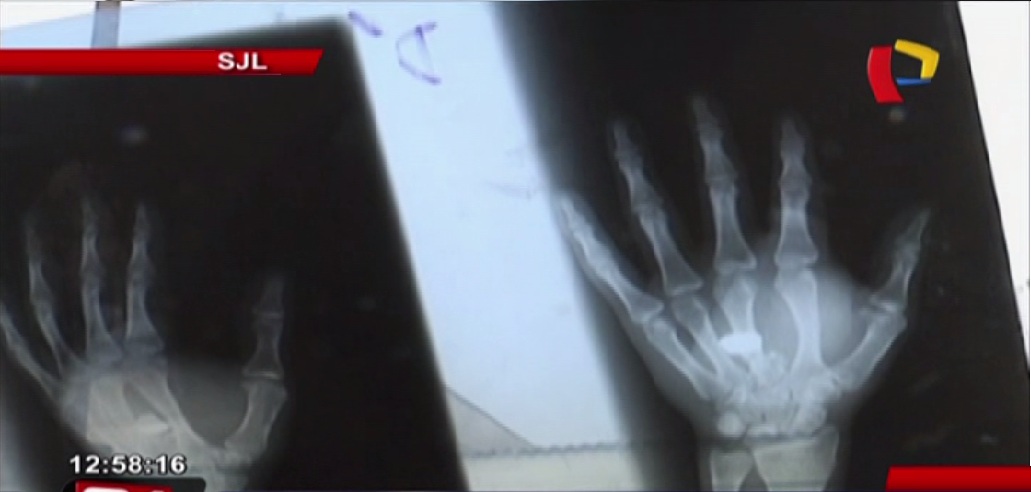

Aarón Robelo Flores recibió un impacto de bala en la mano cuando se encontraba en la cuadra 15 de la avenida Central, en San Juan de Lurigancho. Según los familiares del herido, el suboficial Cristian Erazo Campos realizó varios disparos desde el tercer piso de su vivienda, sin embargo no quiso hacerse responsable del hecho.